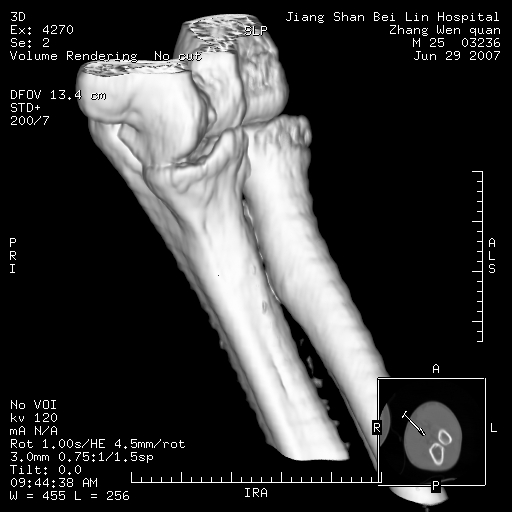

标题: CT8866:男27岁,正常吗?

患者男27岁,2007年3月查出患上肘关节滑膜结核,此后行手术滑膜剥除,今查ct

看一下上面的桡骨粗隆有问题吗?

桡骨粗隆有问题,术后改变

桡骨骨皮质破坏,结合病史考虑结核